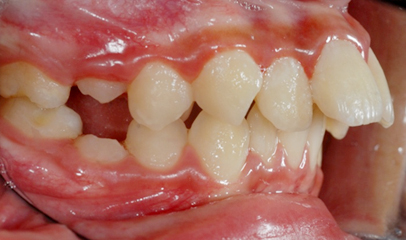

발치 돌출입 교정

전후 사례

발치 교정, 치료기간 약 2년

Before